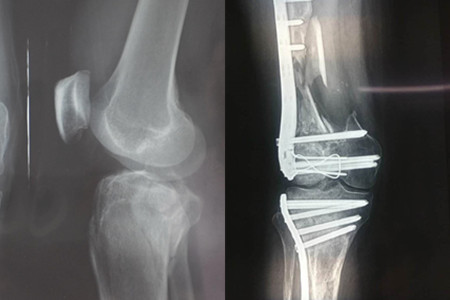

这个伤残等级鉴定表不仅可以让我们得到自己应该得的赔偿,还能给我们的心理上一点安慰,让我们不必要担心自己的身体出现了某些问题,如果等级不是很高的话,那应该只是轻微的骨折,如果等级很高的话,说明身体状况出现了严重的问题,需要及时治疗才行。